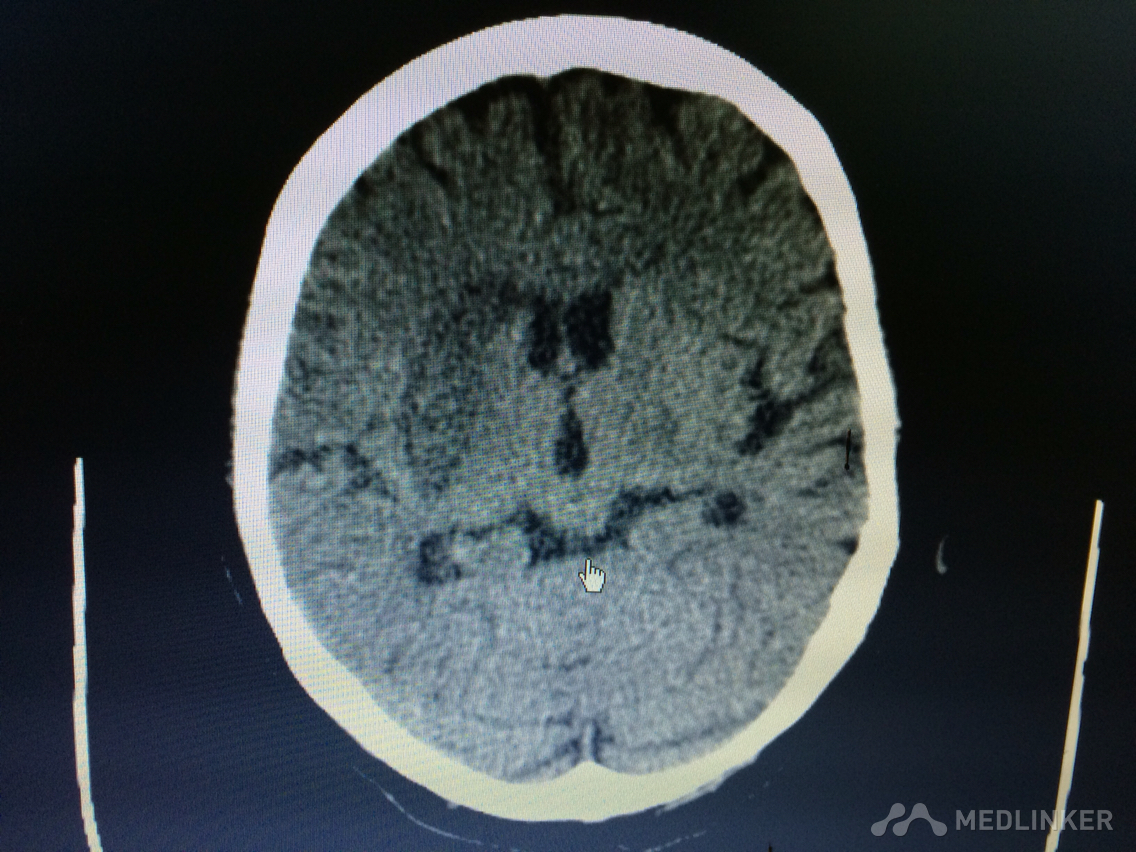

下面的CT梗塞灶,请问对应血管?